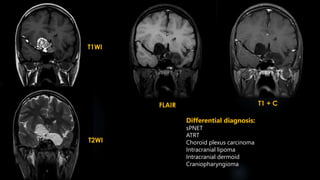

Intracranial Teratoma  accountfor the largest proportion of fetal intracranial neoplasms  divided into two broad categories: - intra- and extra-axial  Intra-axial teratomas present antenatally due to increasing head circumference; tend to occur supratentorially  Extra axial teratomas usually present in childhood or early adulthood; commonly arise in the pineal or suprasellar regions; obstructive hydrocephalus, Parinaud syndrome

• 52.

Intracranial Teratoma (contd.) CT:  Intracranial teratomas are often seen as large lesions at presentation  tumours typically demonstrating a mixture of tissue densities and signal intensity  demonstrate at least some fat and some calcification, which is usually solid / "clump-like"  They usually have cystic and solid components, contributing to an irregular outline.  Solid components demonstrate variable enhancement  MRI:  T1 - hyperintense components due to fat and proteinaceous/lipid rich fluid; intermediate components of soft tissue; hypointense components due to calcification and blood products  T1 C+ (Gd) - solid soft tissue components show enhancement  T2 - again mixed signal from differing components

• 53.

T1WI T2WI FLAIR T1 +C Differential diagnosis: sPNET ATRT Choroid plexus carcinoma Intracranial lipoma Intracranial dermoid Craniopharyngioma